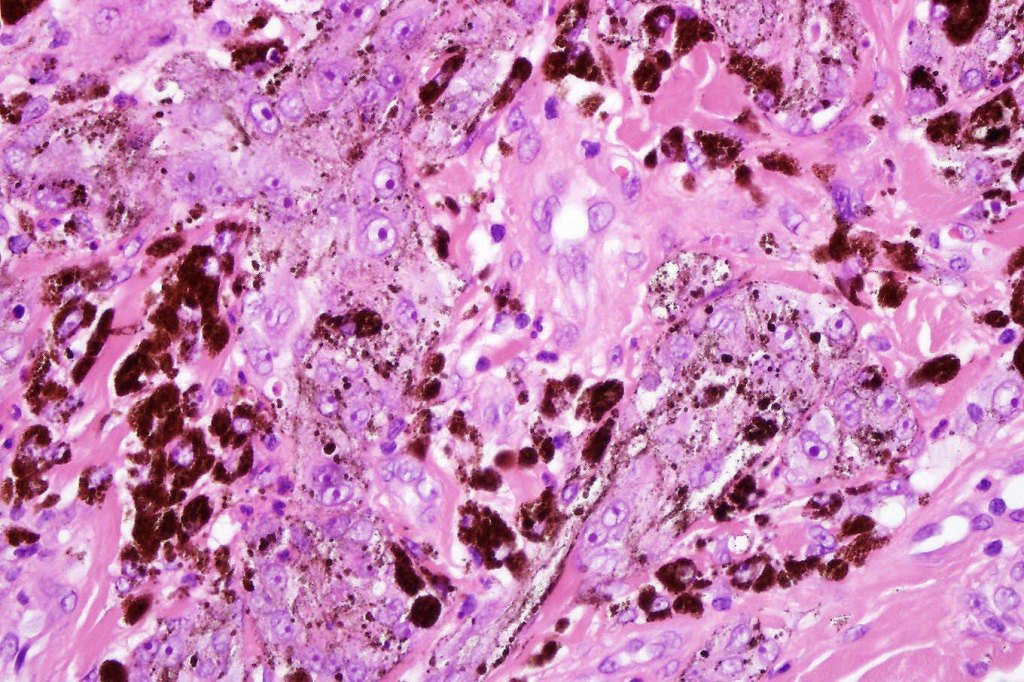

•Composed of an admixture of large epithelioid melanocytes with vesicular nuclei containing a very prominent nucleolus (fried egg cells), spindle cells, dendritic cells & melanophages

•The epithelioid cells are typically very uniform

•Few mitoses